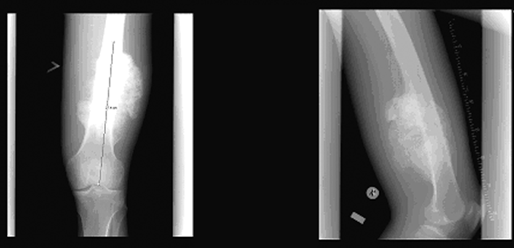

Рентгенологически гигантоклеточная опухоль характеризуется наличием очага деструкции, в большинстве случаев центрально расположенного в метаэпифизарных отделах длинных трубчатых костей, отграниченного от неизмененной ткани слабо выраженной зоной склероза, которая зависит от длительности существования и скорости роста опухоли (чем выраженнее склероз, тем медленнее растет и длительнее существует опухоль, что свидетельствует о доброкачественности процесса) (рис. 1). Очаг деструкции при значительных размерах опухоли вызывает истончение и вздутие кортикального слоя. Возможно разрушение кортикального слоя с выходом опухоли в экстраоссальные мягкие ткани, что указывает на возможность инфильтрирующего роста. Очаг деструкции нередко имеет ячеистое строение. Остеолитическая деструкция свидетельствует о более агрессивном течении опухоли. Гигантоклеточная опухоль относится к условно доброкачественным опухолям. Возможно озлокачествление опухоли. Частота озлокачествление возрастает после лучевой терапии в дозе более 40 Гр и при рецидивах после нерадикальных операций. Рентгенологические признаки озлокачествления гигантоклеточной опухоли: быстрое увеличение преимущественно остеолитического очага деструкции с потерей четкости контуров и исчезновением зоны склероза, с разрушением кортикального слоя, возможным его разволокнением и появлением козырька Кодмена и экстраоссального компонента опухоли. КТ и МРТ вносят дополнительную информацию о степени распространенности опухоли, необходимую при планировании хирургического лечения. Возможны единичные и множественные метастазы в легкие.

Рисунок 1. Рентгенологическая картина гигантоклеточной опухоли проксимального отдела плечевой кости